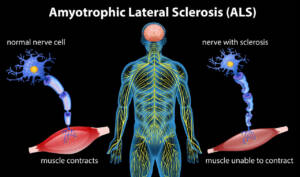

Nelle malattie degenerative: per il trattamento di sclerosi multipla,

SLA,

Parkinson

e demenza senile precoce.